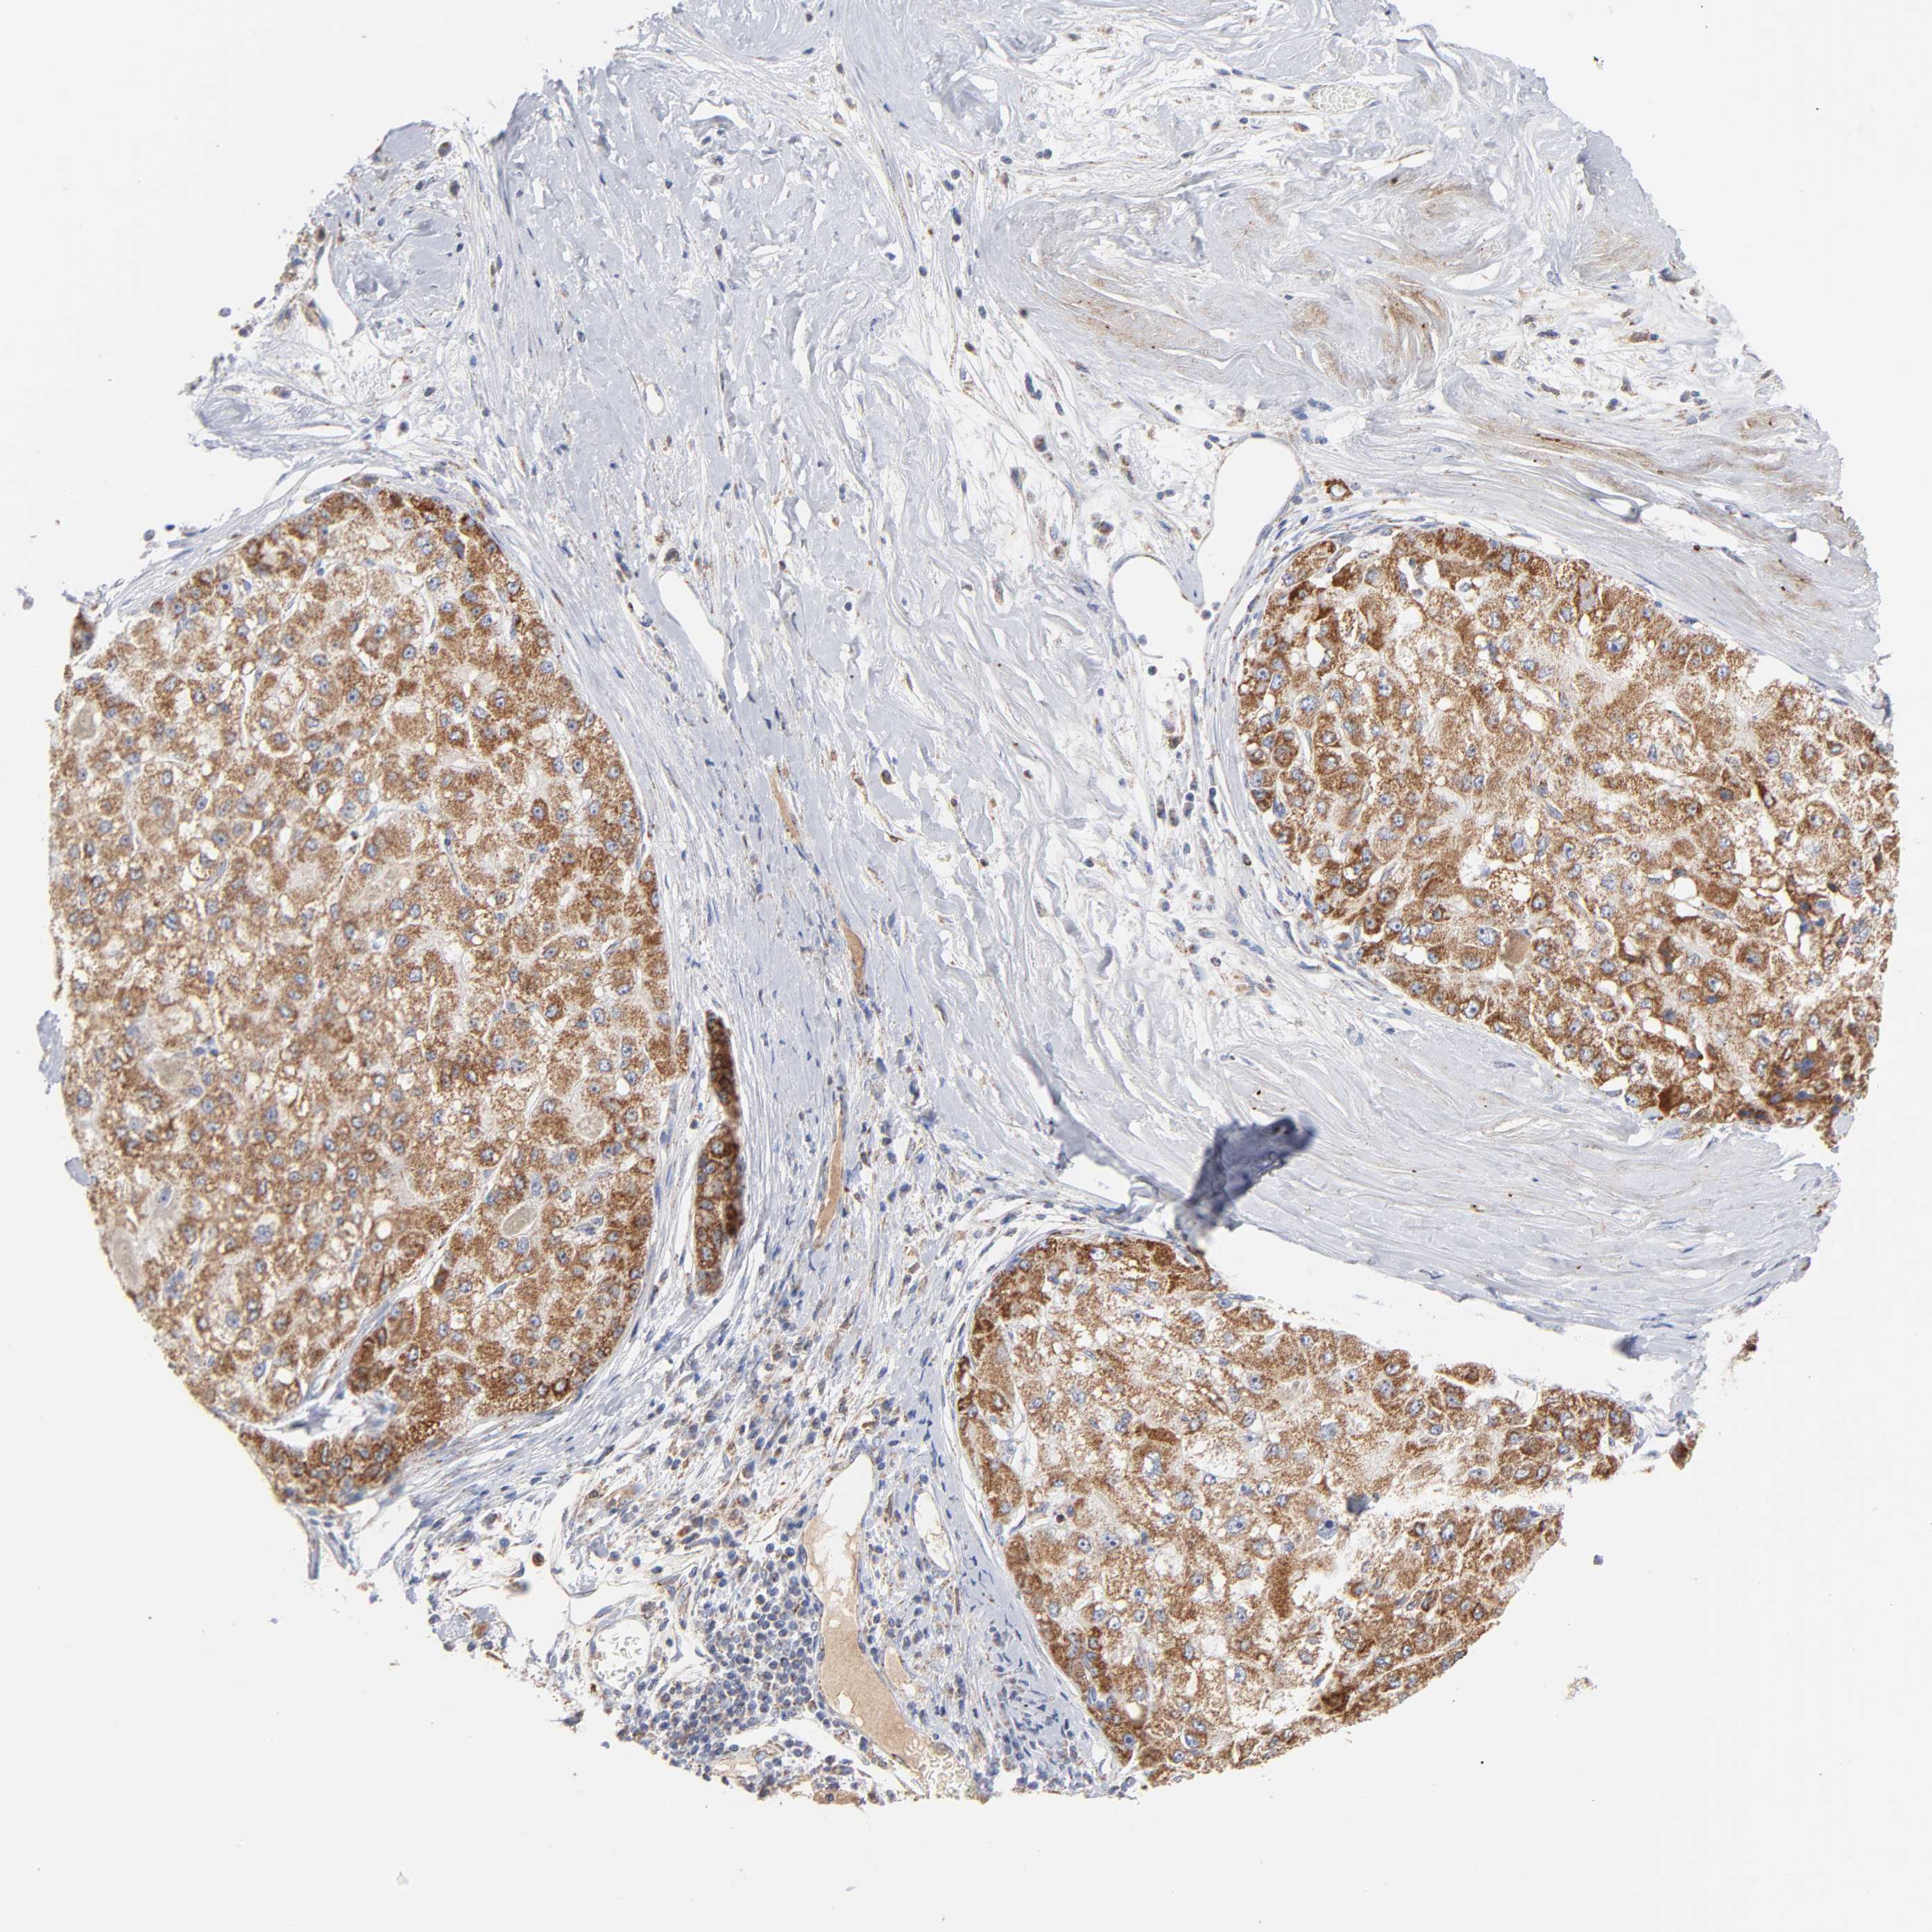

LIVER CANCER - Protein expressioni

A mouse-over function shows sample information and annotation data. Click on an image to view it in a full screen mode. Samples can be filtered based on level of antibody staining by selecting one or several of the following categories: high, medium, low and not detected. The assay and annotation is described here.

Note that samples used for immunohistochemistry by the Human Protein Atlas do not correspond to samples in the TCGA dataset.

Antibody stainingi

Antibody staining in the annotated cell types in the current human tissue is reported as not detected, low, medium, or high, based on conventional immunohistochemistry profiling in selected tissues. This score is based on the combination of the staining intensity and fraction of stained cells.

Each image is clickable and will lead to virtual microscopy that enables deeper exploration of all samples and also displays staining intensity scores, fraction scores and subcellular localization as well as patient and tissue information for each sample.

Antibody HPA001825

Antibody CAB003857

Staining

High

Medium

Low

Not detected

Intensity

Strong

Moderate

Weak

Negative

Quantity

>75%

75%-25%

<25%

None

Location

Nuclear

Cytoplasmic/membranous

Cytoplasmic/membranous,nuclear

Cholangiocarcinoma

Carcinoma, Hepatocellular, NOS